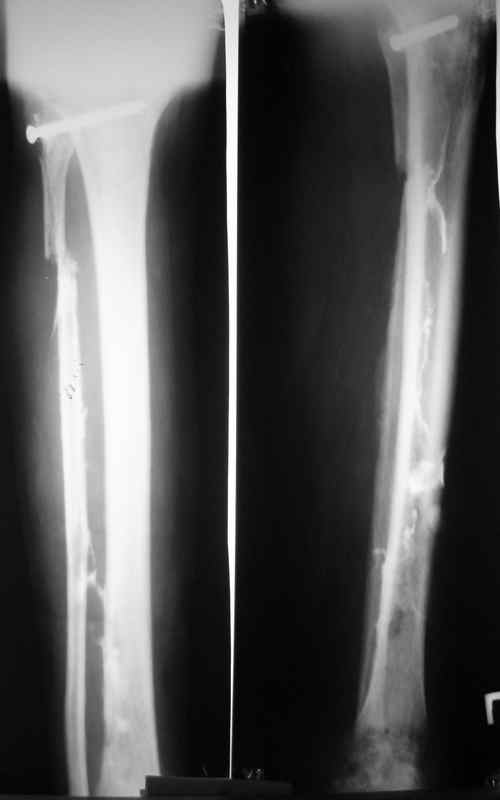

Доброго времени суток, коллеги! Сегодня поступил больной с остеомиелитом

голени, 29 лет.

Травма - январь 2007 года, <Открытый перелом малоберцевой кости,с

повреждением малоберцевого нерва>. Первичных снимков нет. лечился в

одной из районных больниц xUSSR. Обратился ко мне в сентябре 2007 года,

сжалобами на наличие свищей,неопорность конечности.Был направлен после

выполнения фистулографии (см. фото) в областной  центр по лечению

остеомиелита. Там была выполнено 2 операции:  резекция малоберцевой

кости, и повторный дебридмент. Последнее вмешательство около месяца

назад. Послеоперационные снимки на фото. В течении месяца получал